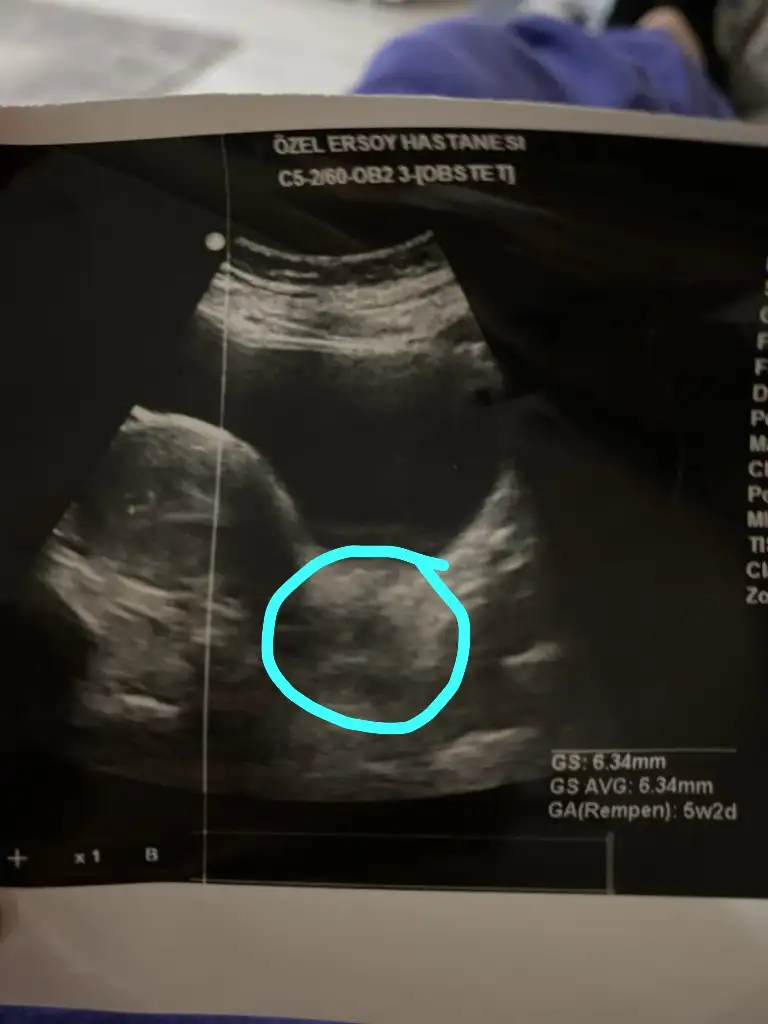

Beta değerim 1299,45 çıktı ultrasonda kese 6.34 mm

Ama doktor bana dış gebelik olabilir 2 gün sonra tekrar geleceksin dedi hayatımın şokunu yaşıyorum tekrardan. Diğer doktor rahme yerleşmiş dedi anlamadım Kızlar yemin ederim.